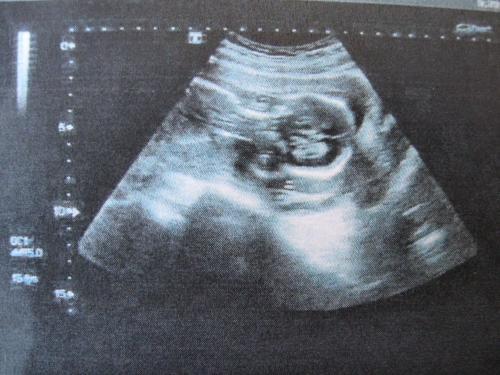

有很多準媽媽比較關心懷孕期間的B超檢查,從直覺上大部分人都會認為做B超可能有輻射,對胎兒可能會產生一些影響,因此有些準媽媽特別在意B超檢查的次數和時間。那么本文第一寶寶小編將會對孕期的B超檢查做一個簡單的科普。

1、孕期第一次B超檢查時間是在懷孕18-20周,可確定懷的是單胎還是多胎,并可測量胎兒頭圍等。因為這一階段胎兒B超多項指標誤差較小,便于核對孕齡。

2、孕期第二次檢查時間在懷孕28-30周。做B超目的是了解胎兒發育情況,是否有體表畸形,還能對胎兒的位置及羊水量有進一步的了解。

3、孕期最后一次是在懷孕37-40周。做B超檢查的目的是確定胎位、胎兒大小、胎盤成熟程度,有無臍帶纏頸等,進行臨產前的最后評估。